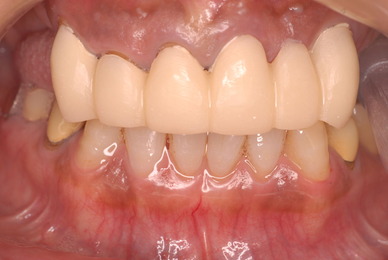

歯をいじられ体も心もボロボロになった患者さんからの手紙です。マスコミや権威などがいかにいい加減かわかります。歯は触らないほうがよろしいのです。

そもそも歯を触り何らかの金属やセラミックを入れる行為そのものが医学的には傷害処置ですから、なるべく避けるべき物なのです。